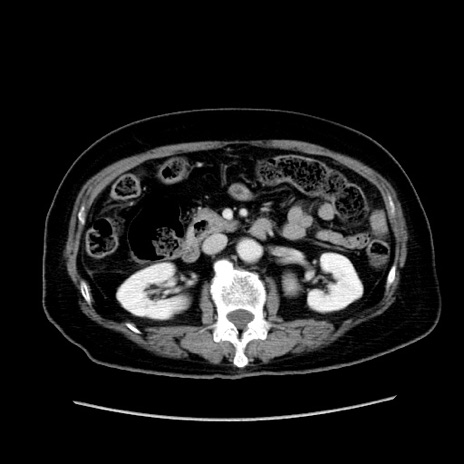

症例19(横断像)

【症例】80歳代女性

【主訴】下腹部痛

【現病歴】約8時間前より下腹部痛の出現あり、救急外来受診。

【既往歴】両側付属器切除

【身体所見】意識清明、下腹部正中に手術痕あり、その部位に一致して圧痛と反跳痛あり。腸蠕動音は亢進。

【データ】WBC 9300、CRP 0.15